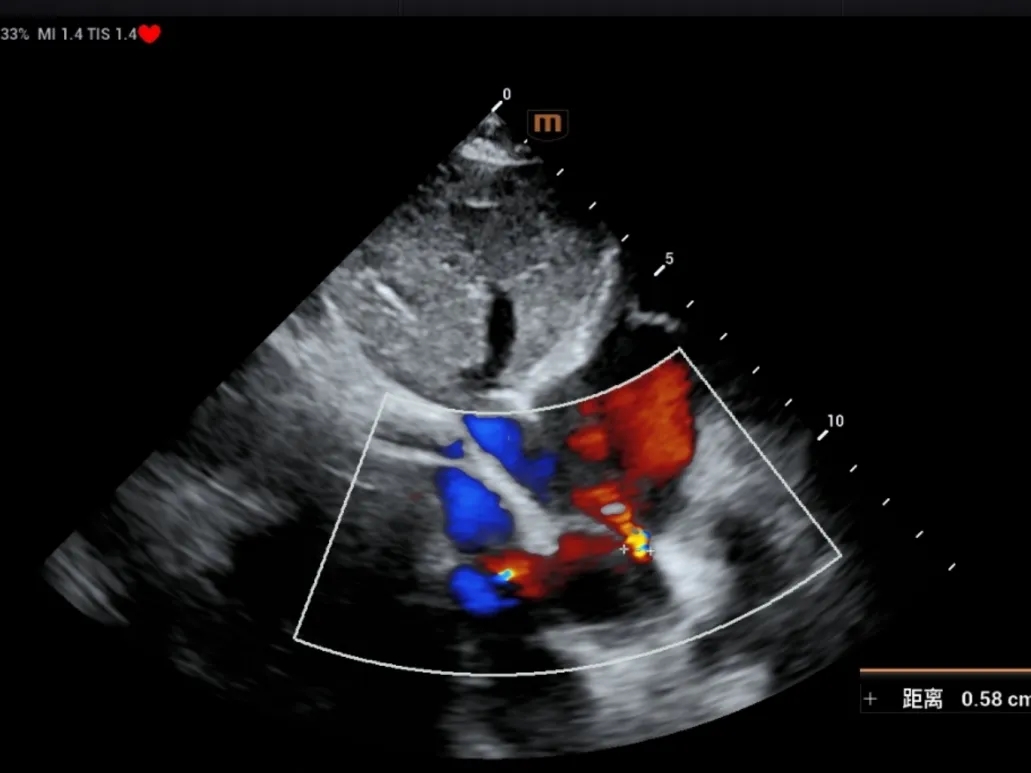

DSA可见Mark点聚集到一起,多普勒显示即刻阻流效果良好

锁定后评估

彩色多普勒血流成像显示无残余分流存在